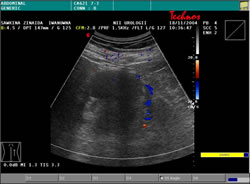

УЗИ: |

|